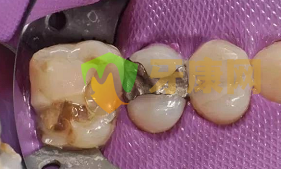

3、窩溝充填

最后才是窩溝充填,這個時候患者已基本感覺不到疼痛,調配充填材料填入窩洞中,雕刻外形,要注意除去超過咬合面過高的部分,以免造成醫源性的咬合創傷。

4、塑型立固、打磨牙齒

最后再使用LED光固化燈照射,使得樹脂加溫后立固,最后把充填物表面的細微的凸凹不平之處磨平,使牙齒棱角平滑。